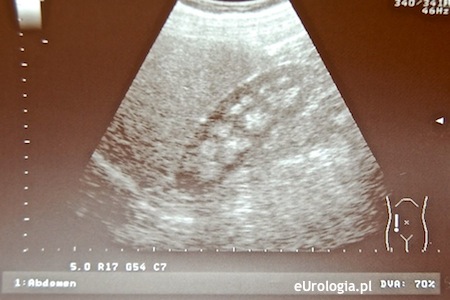

Nefrokalcynoza